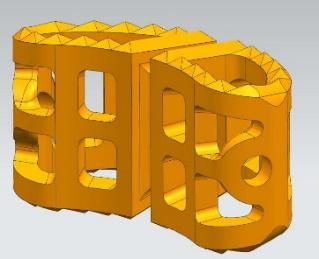

根据手术方案中的脊柱形态进行测量,定制个性化的假体和截骨导板。

定制个性化融合

假体置于病例模型中